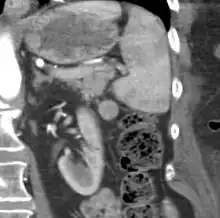

CT scan of an accessory spleen (circular object in center of image) between the spleen and left kidney.